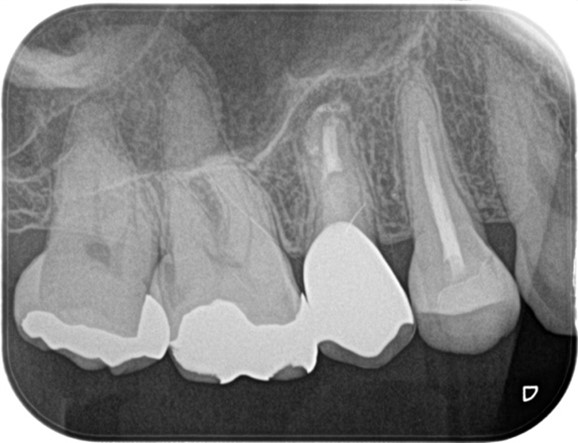

この患者様は、前医での根管治療がうまく行っていないことを主訴に当院の精密根管治療カウンセリングを受診されました。初診時の段階で歯肉の炎症が著しく、根尖部を指で押すと痛みを訴えておられました。診査したところ右上5番の根尖には黒い透過像(写真2黄色囲み線)が確認できるのと、歯質は大きく削られており(写真2赤線部)、残存する歯質は(写真2青線部)非常に薄くなっていることが確認できました。

初診の時点では破折等の所見は確認されなかったことら、治療は可能と判断しましたが、歯質が薄いことから将来的な費用対効果が低くなることも考えられました。